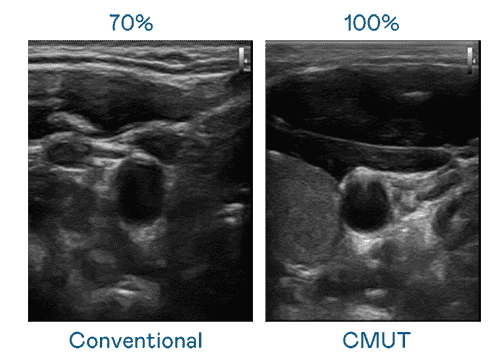

CMUT 技术是一种用电容式微机电元件来产生超音波讯号的技术。。。。与传统 PZT 压电式技术相比,,CMUT 频宽增加 30%,,,更宽频的超音波讯号让影像解析度大幅提升,,,,是实现高影像品质医疗超音波扫描、、促进精准医疗发展的关键技术。。

大频宽带来超清晰影像

超音波影像的解析度高低,,,,首先取决于探头能发出的讯号频宽。。杏悦2 CMUT 可提供高清晰的超音波讯号,,,,提供高频宽、、、、高灵敏度、、、影像纹理细节更高的超音波影像,,,协助医护人员缩短影像判读时间及利用精准的医疗影像进行诊断。。